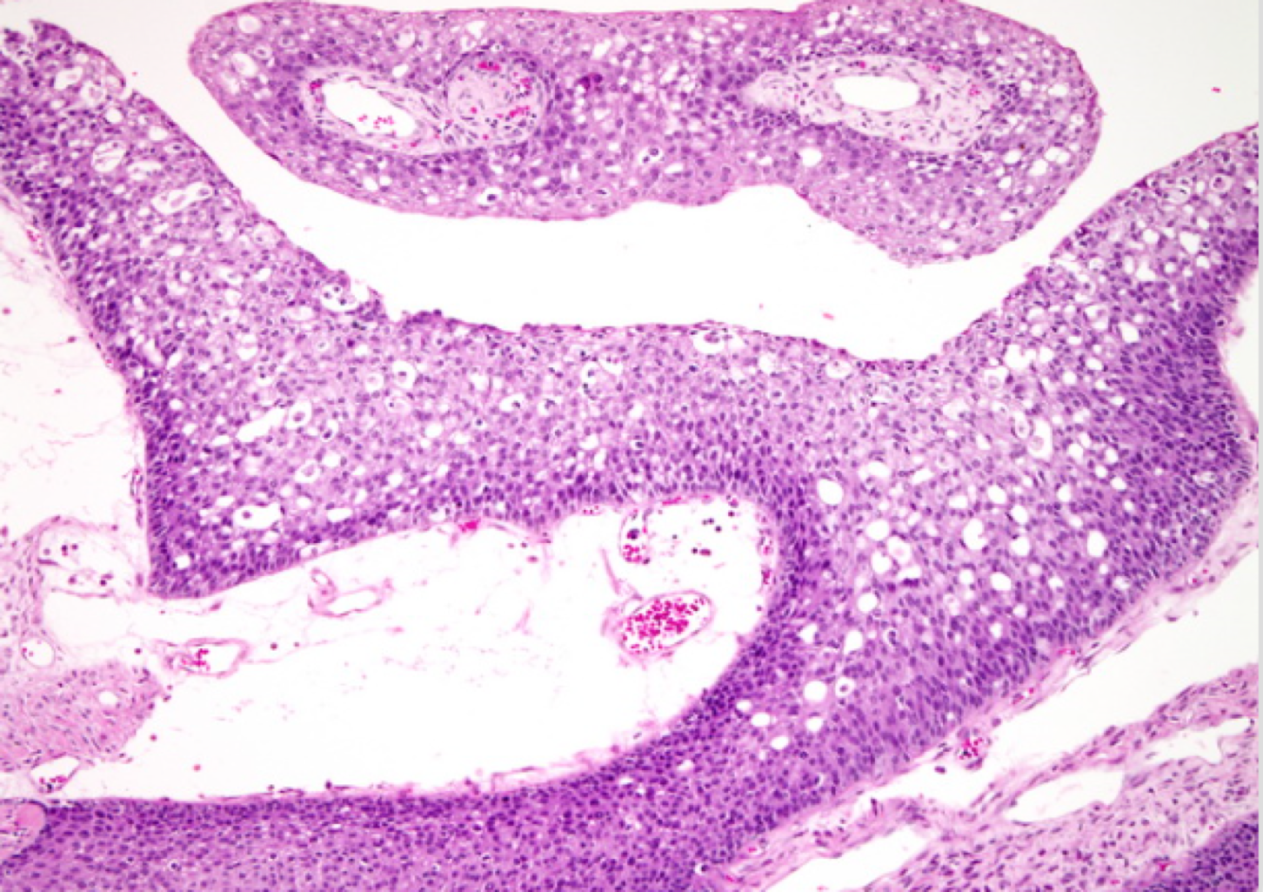

The Ovary Part 1 class deals with normal ovarian structure, non neoplastic lesions of the ovary including cysts and surface epithelial ovarian tumours.